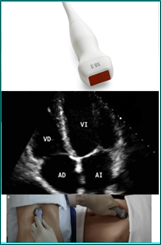

SECTORIALES

Formato de imagen triangula. Se usa en estructuras profundas como: exploraciones cardiacas y abdominales, permite el abordaje costal.